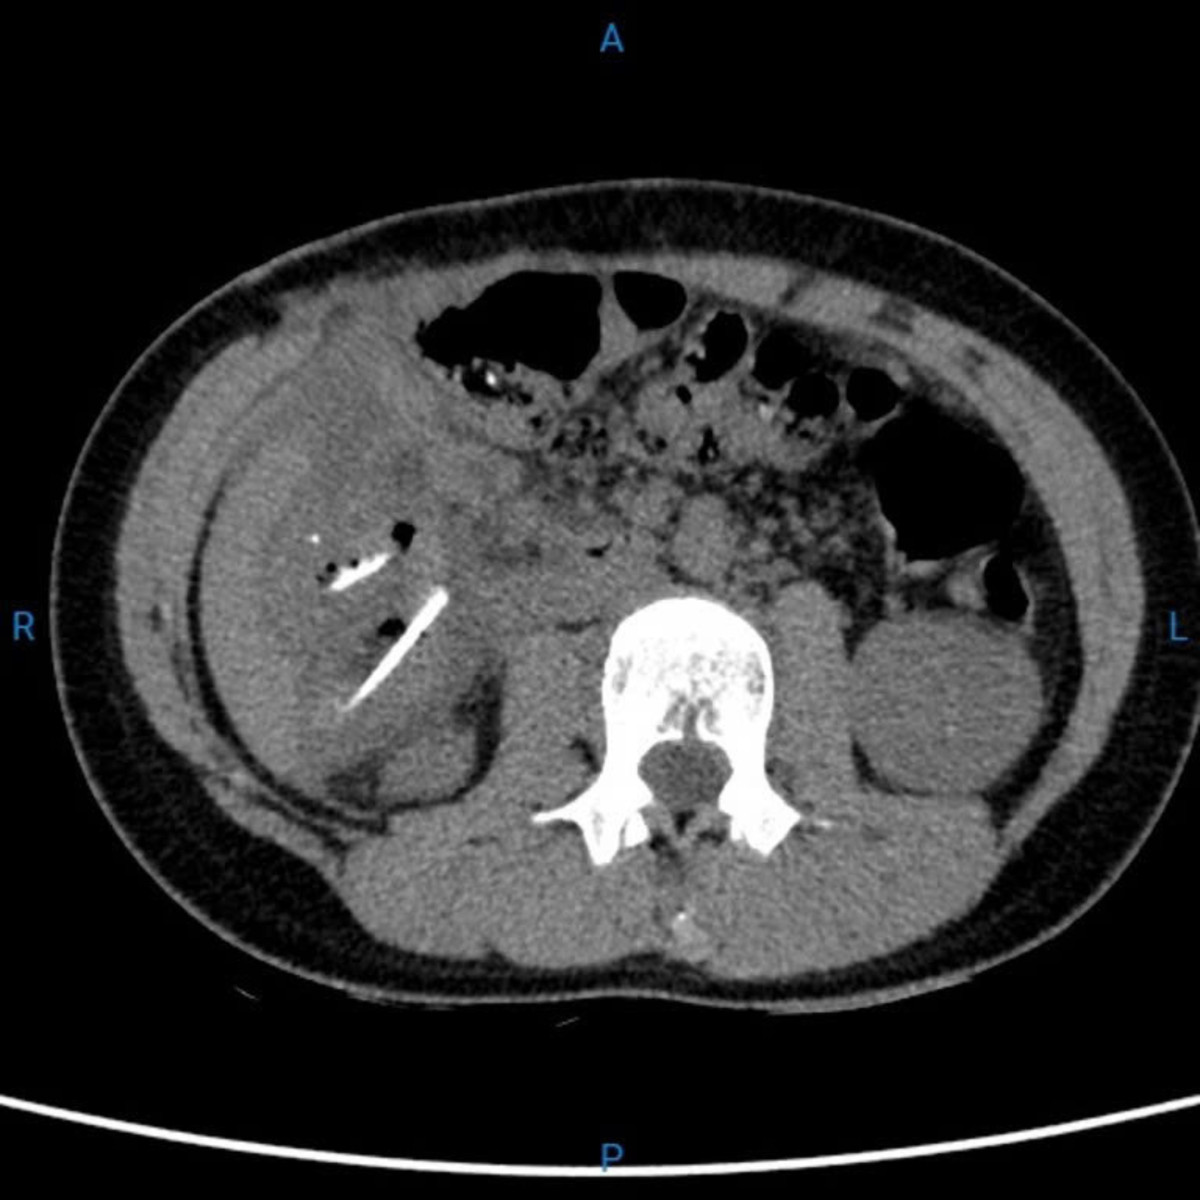

Hình CT scan bụng cho thấy những hình ảnh sáng của xương vùng hông bên phải. Ảnh BV

Kết quả chụp CT-scan bụng khẩn cho thấy nhiều dị vật nằm rải rác trong ổ bụng và lòng ruột non. Trẻ được các bác sĩ chuyển mổ khẩn ngay trong đêm.